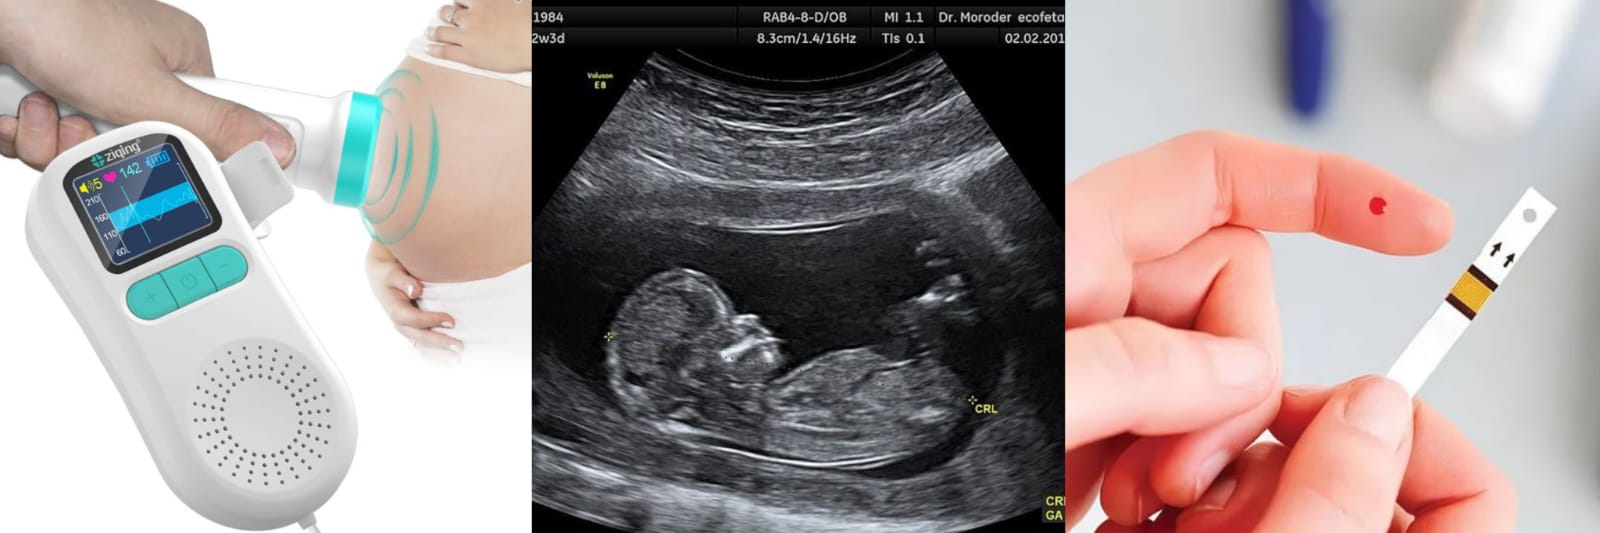

Estudios diagnósticos en el embarazo

Las pruebas de embarazo son exámenes que se utilizan para detectar la presencia de la hormona gonadotropina coriónica humana (hCG) en la orina o la sangre de una mujer. Esta hormona se produce durante el embarazo cuando un óvulo fecundado se implanta en el útero.

Tipos de pruebas diagnósticas en la gestación